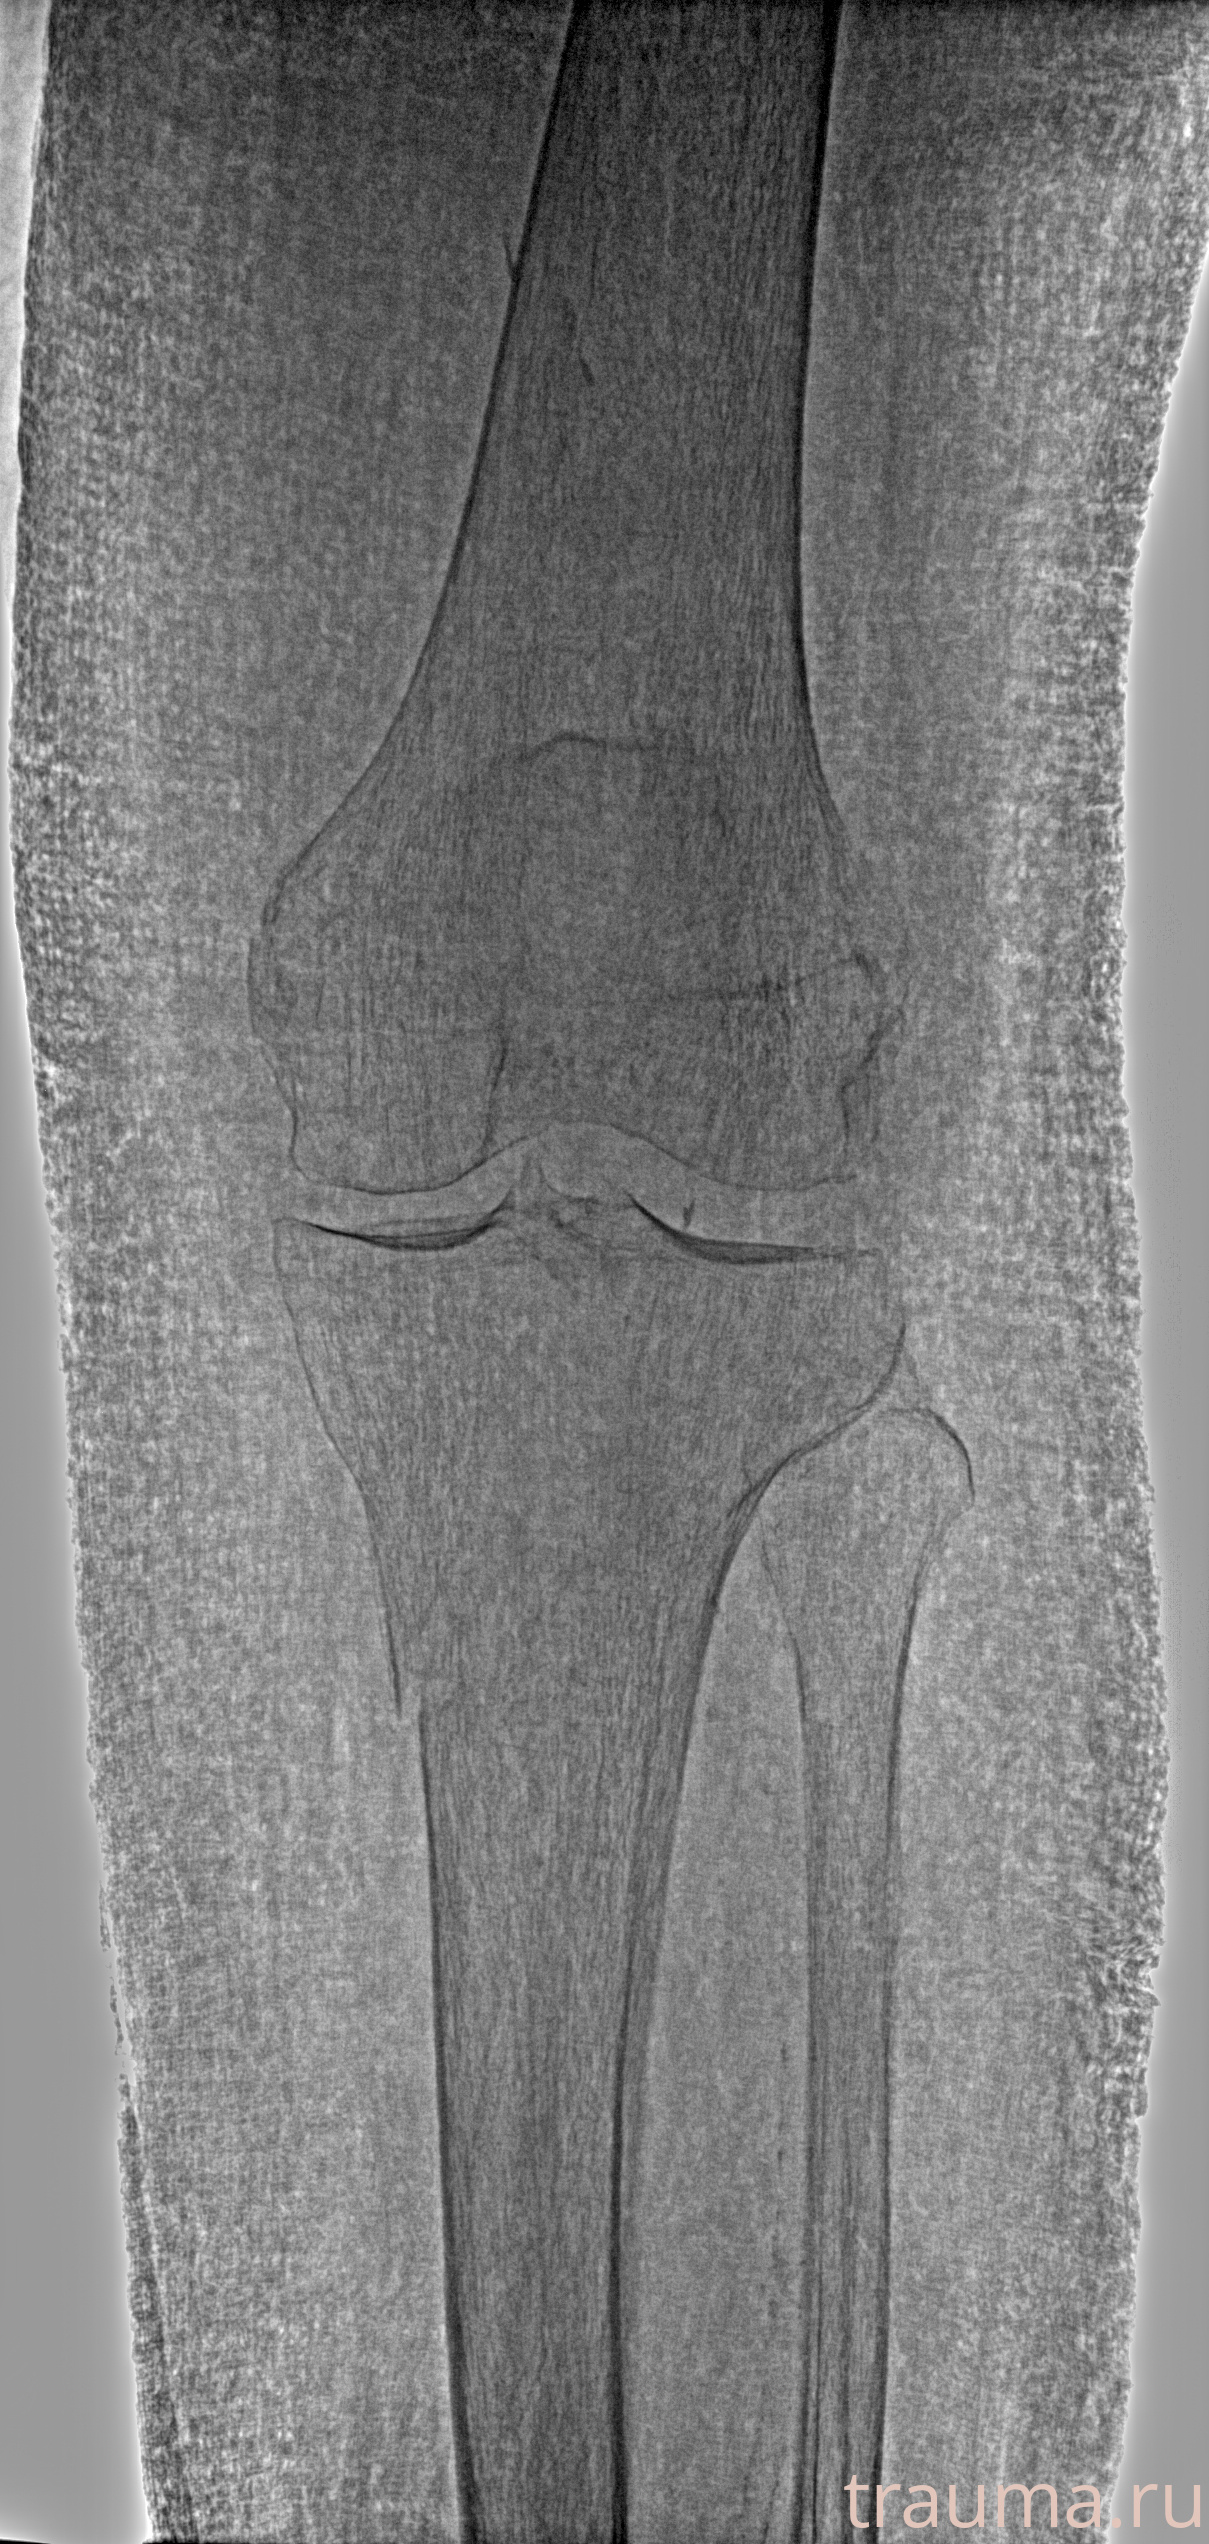

Рентгенограммы

Рентген на дому: по вашему адресу приезжает врач-рентгенолог, травматолог-ортопед с мобильным рентгеновским аппаратом, проводит диагностику травмы или заболевания, делает необходимые рентгенограммы, дает рекомендации по дальнейшему лечению. Получить качественные снимки в домашних условиях возможно благодаря уникальной методике, разработанной МосРентген Центром для института  Склифосовского